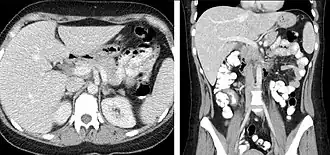

FIGURE 2. Contrast enhanced CT demonstrating parenchymal enhancement of the intra-abdominal organs in the portal venous phase (axial left, coronal reformat right).

FIGURE 7. Selected images from a renal mass specific protocol CT. Corticomedullary phase (axial 7a) demonstrates peripheral enhancement of the renal cortex with minimal opacification of the renal medulla. There is a large renal cell carcinoma in the left kidney (right in image) which can be differentiated from the normal renal parenchyma by the heterogeneous and differential enhancement. The renal artery and vein are opacified in this phase as well. The collecting system is not opacified (coronal reformat 7b). In the parenchymal phase, the renal cortex and the medulla are enhancing. The renal cell carcinoma in the left kidney is not as well defined when compared to the corticomedullary phase images, but is actually slightly more conspicuous. There is some contrast noted within the collecting system during this phase (7c).